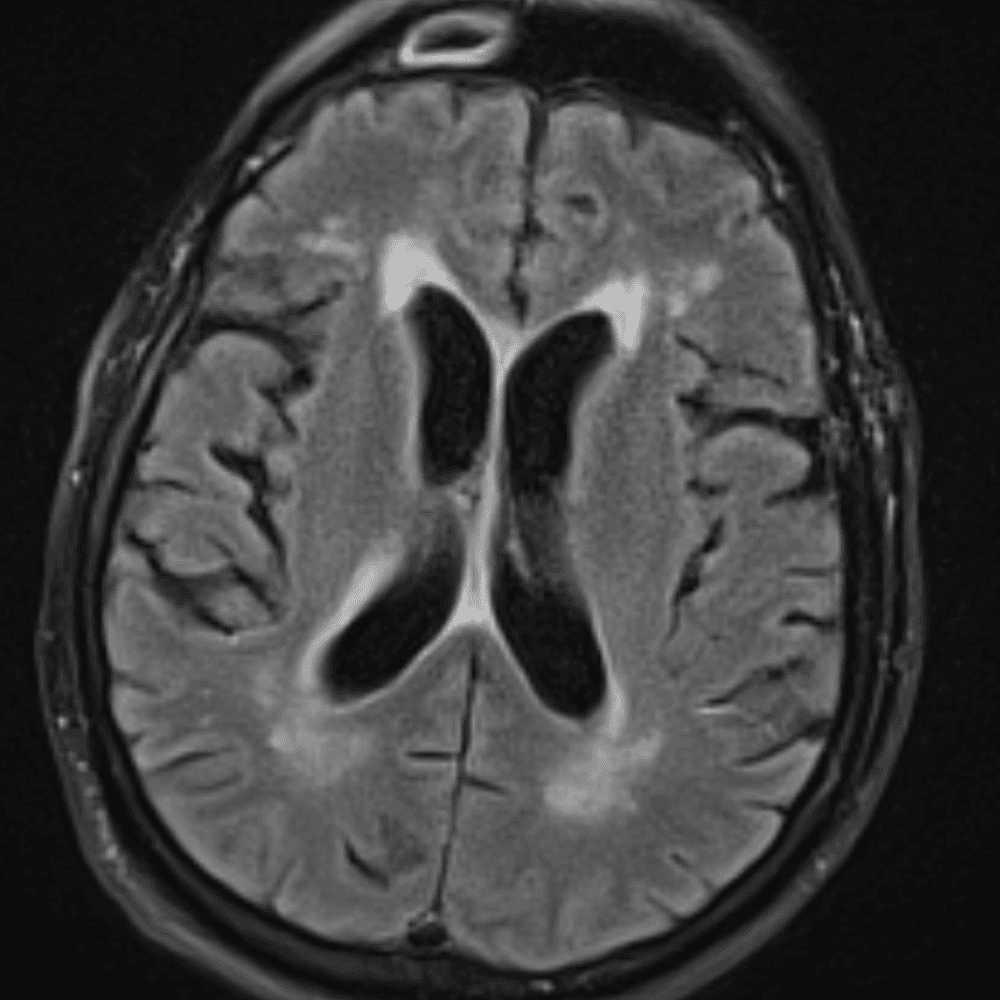

์—ฐ์Šต

๋ฏธ๋ฌ˜ํ•˜๊ฑฐ๋‚˜ ์–ด๋ ค์šด ์‚ฌ๋ก€์™€ ์ผ๋ถ€ ์ •์ƒ ์‚ฌ๋ก€๋ฅผ ํฌํ•จํ•˜์—ฌ ๋‹น์ง์„ ์‹œ๋ฎฌ๋ ˆ์ด์…˜ํ•ฉ๋‹ˆ๋‹ค.

50 ์‚ฌ๋ก€